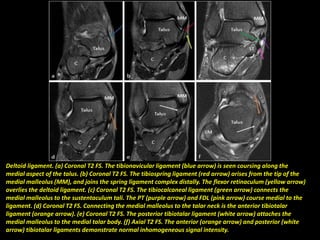

Deltoid ligament. (a) Coronal T2 FS. The tibionavicular ligament (blue arrow) is seen coursing along the

medial aspect of the talus. (b) Coronal T2 FS. The tibiospring ligament (red arrow) arises from the tip of the

medial malleolus (MM), and joins the spring ligament complex distally. The flexor retinaculum (yellow arrow)

overlies the deltoid ligament. (c) Coronal T2 FS. The tibiocalcaneal ligament (green arrow) connects the

medial malleolus to the sustentaculum tali. The PT (purple arrow) and FDL (pink arrow) course medial to the

ligament. (d) Coronal T2 FS. Connecting the medial malleolus to the talar neck is the anterior tibiotalar

ligament (orange arrow). (e) Coronal T2 FS. The posterior tibiotalar ligament (white arrow) attaches the

medial malleolus to the medial talar body. (f) Axial T2 FS. The anterior (orange arrow) and posterior (white

arrow) tibiotalar ligaments demonstrate normal inhomogeneous signal intensity.